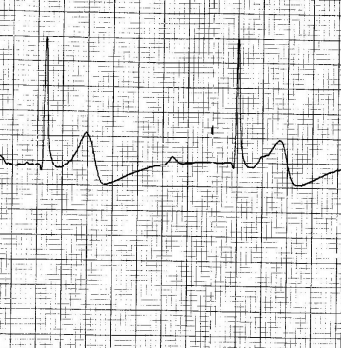

EsAmb : ECG N°2

Les études de cas sur les ECG par les étudiants ambulanciers de Genève avec les commentaires et la correction du Dr Marc Zimmermann (cardiologue à Genève) : ECG N°2 par Emmanuelle BLASER Voir l'étude de cas ECG N°2 Ce…

EsAmb : ECG N°4

Les études de cas sur les ECG par les étudiants ambulanciers de Genève avec les commentaires et la correction du Dr Marc Zimmermann (cardiologue à Genève) : ECG N°4 par Cédric GOLAZ Voir l'étude de cas ECG N°4 Cette n…

EsAmb : ECG N°3

Les études de cas sur les ECG par les étudiants ambulanciers de Genève avec les commentaires et la correction du Dr Marc Zimmermann (cardiologue à Genève) : ECG N°3 par Alexandra MATHEZ Voir l'étude de cas ECG N°3 Cet…

EsAmb : ECG N°1

Les études de cas sur les ECG par les étudiants ambulanciers de Genève avec les commentaires et la correction du Dr Marc Zimmermann (cardiologue à Genève) : ECG N°1 par Loric STUBY Voir l'étude de cas ECG N°1 Cette ne…